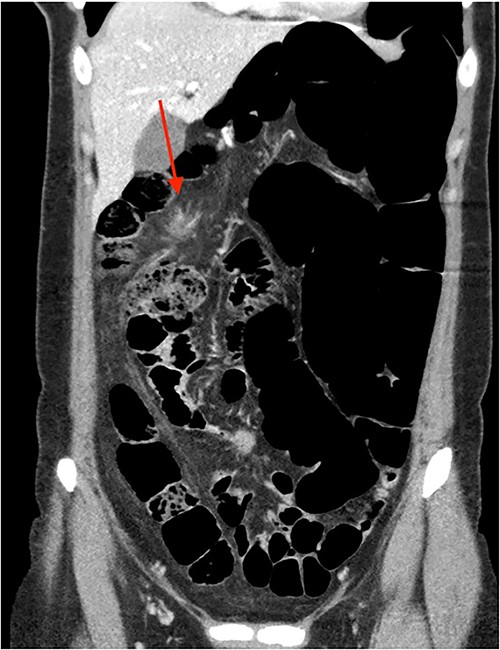

On review of imaging, we noted a CT scan from 2019 which showed swirling and stranding of omentum/mesenteric fat inferior to hepatic flexure (CC 1.8 cm, TV 2.6 cm), with suspicion of internal herniation of the omental/mesenteric fat leading to infarction (Figs 1 and 3). Management of this was unclear as this was at a private hospital in metropolitan Western Australia. A repeat CT scan during her current presentation revealed similar swirling of omentum/mesenteric fat, but with interval increase in size (CC 5.5 cm, TV 7.6 cm). There was associated small bowel dilatation and wall thickening and enhancement with no focal transition point (Figs 2 and 4).

Second, omental torsion is rarely managed conservatively with surveillance imaging. Hence, it is rare that we have CT imaging showing the progression of omental torsion over 4 years, noting the markedly increased dimensions and characteristic mesenteric swirling.